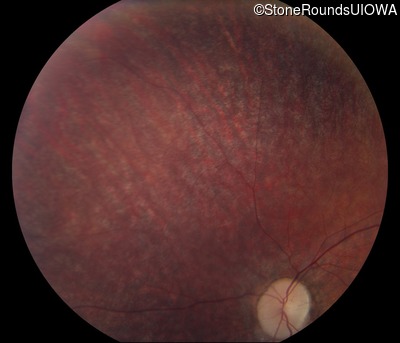

Fundus Photography - Right - 10/100 -1 sc

Exemplar